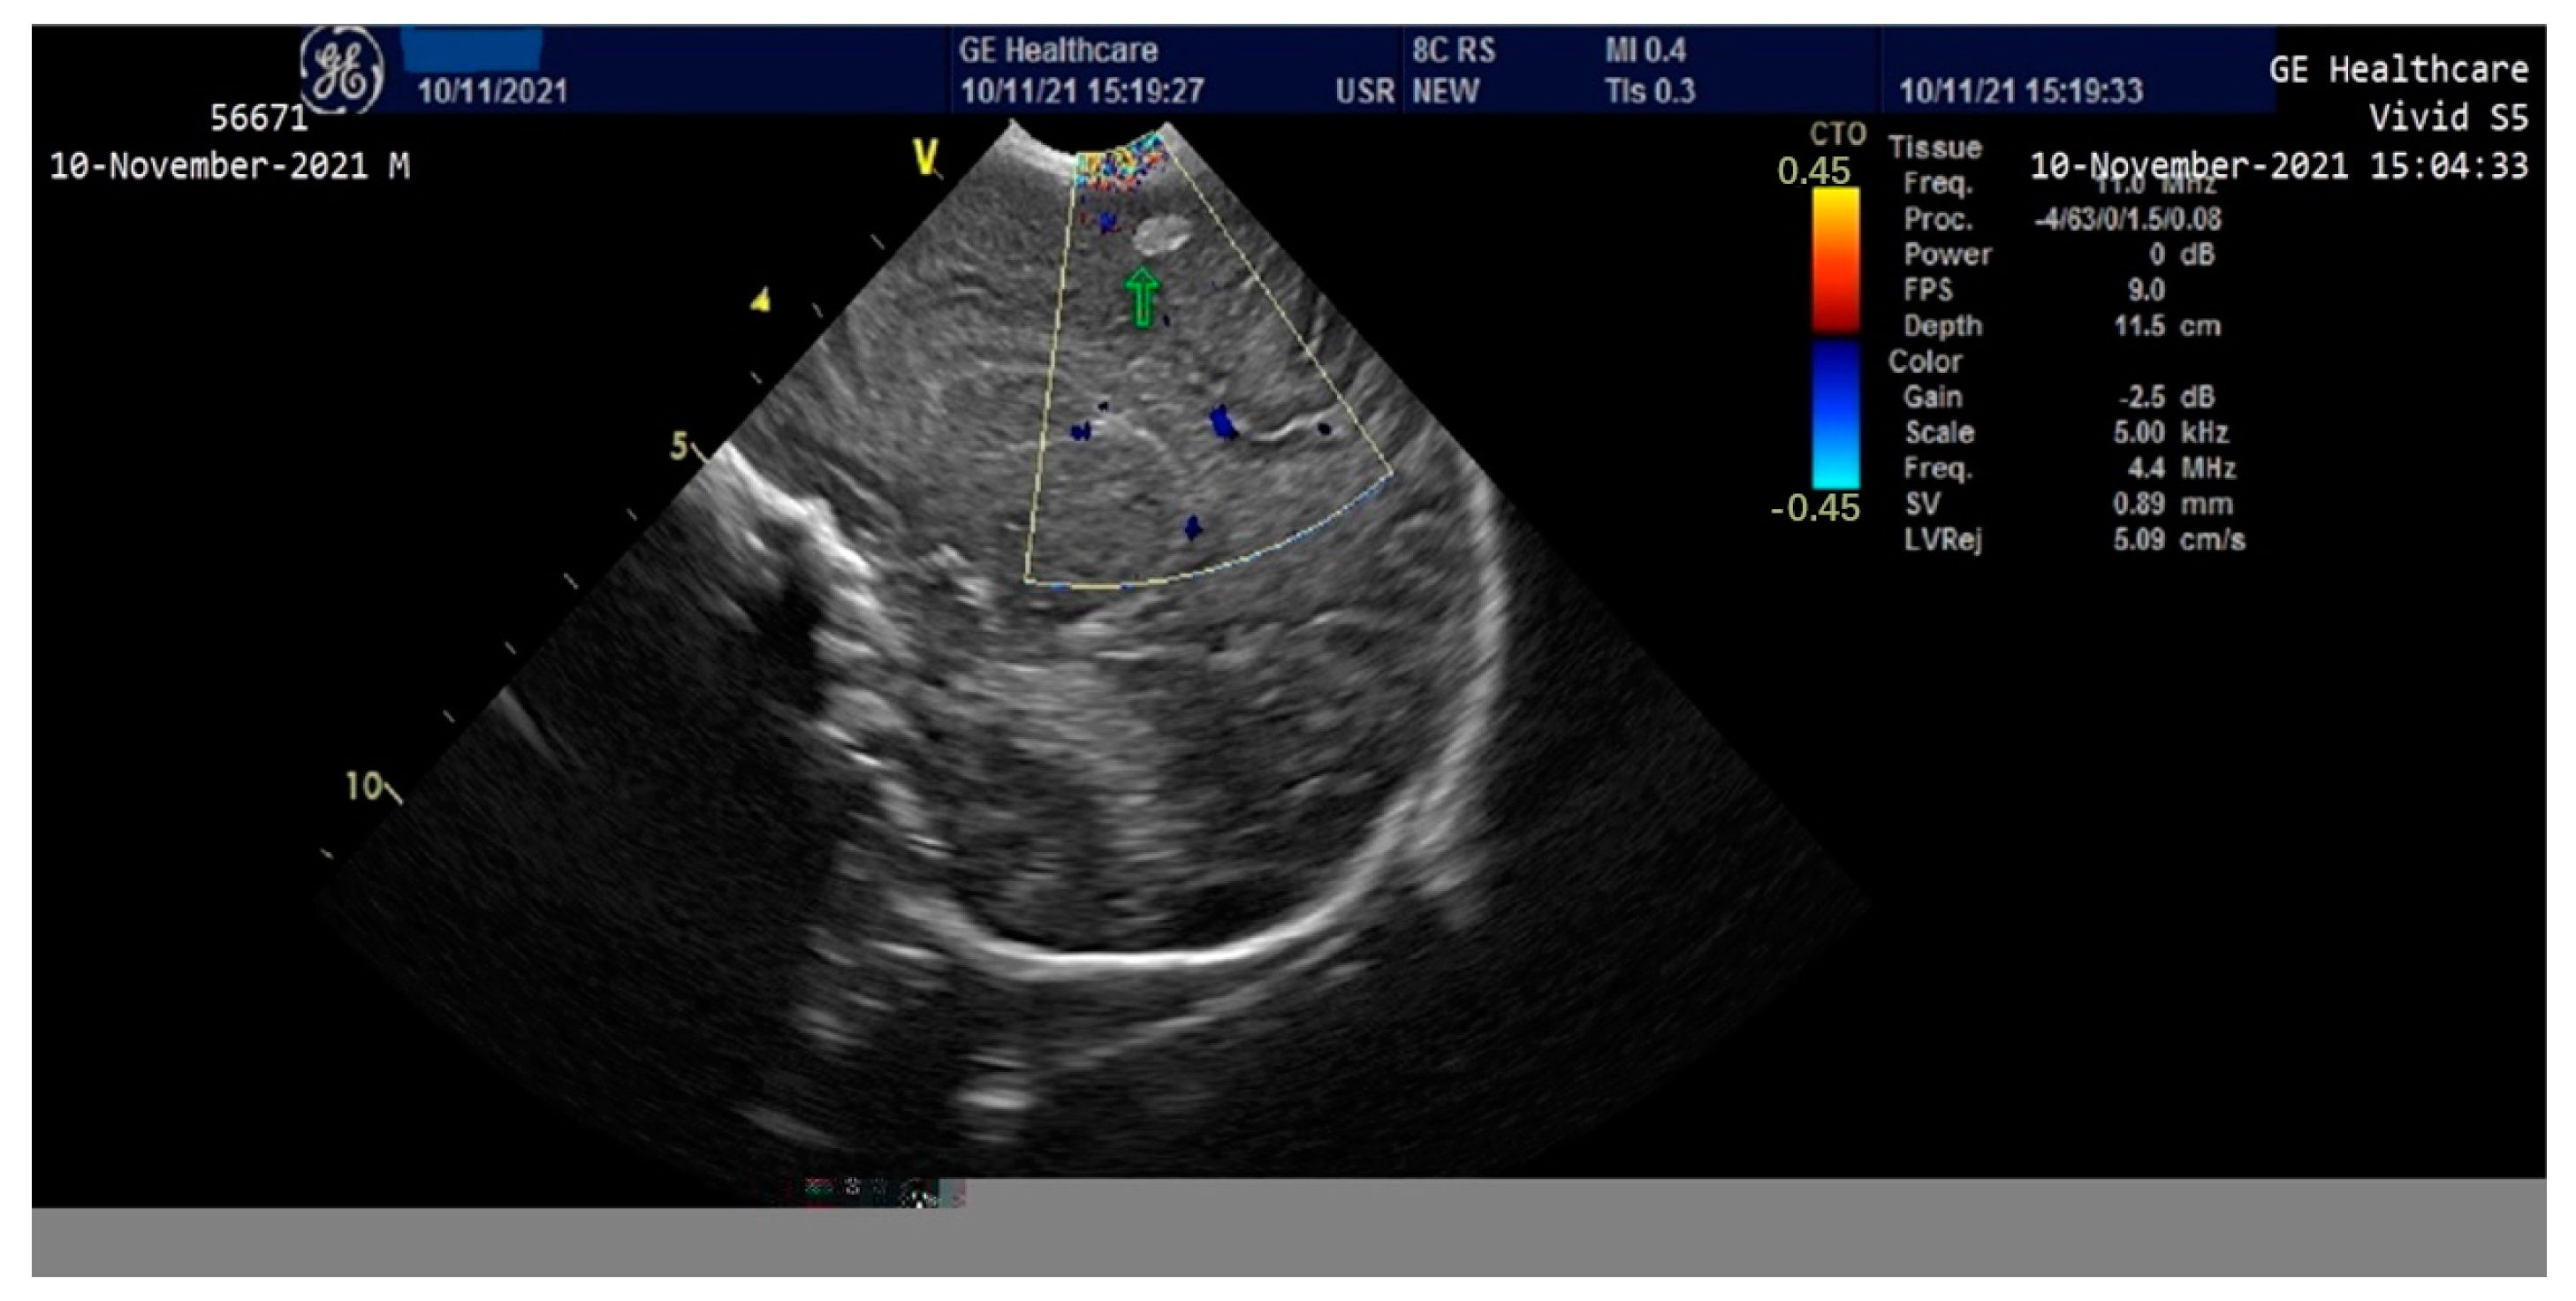

The newborn exhibited hepatomegaly with the right lobe extending caudally. Enlarged hepatic vein and associated splenomegaly were observed on abdominal ultrasound. A cardiac ultrasound revealed mild pulmonary hypertension, mild sized patent ductus arteriosus with left to right shunt, patent foramen ovale with left to right shunt, representing mild cardiac involvement which responded accordingly to the inotrope and vasopressors agents.

On the third day of life, the patient presented clinically and electrically generalized tonic-clonic seizures (aEEG monitoring)—requiring administration of Phenytoin (i.v) and Midazolam until the 8th day, then continued with Phenobarbital per os. A cranial ultrasound performed on the second day of life showed a round-oval hyperechoic image of 0.6/0.4 cm in the relatively superficial left frontal-parietal cerebral parenchyma which evolved to a left periventricular leukomalacia and left porencephalic cyst at one month of age (Figure 3 and Figure 4). The edema gradually reduced and the ascites disappeared; the intestinal transit became functional after 3–4 days and the enteral feeding was initiated. Parenteral nutrition was discontinued after 14 days. Neurological examination at one month of age accompanied by an EEG recording did not show any significant abnormalities. The patient was discharged after 40 days of hospitalization. At 2 months of evaluation, the patient showed an ascending weight curve and significant improvement in cytolysis and hepatic cholestasis.

Figure 3.

Cranial ultrasound in the first 24 h of life with round-oval hyperechoic image 0.6/0.4 cm in the left frontoparietal cerebral parenchyma.